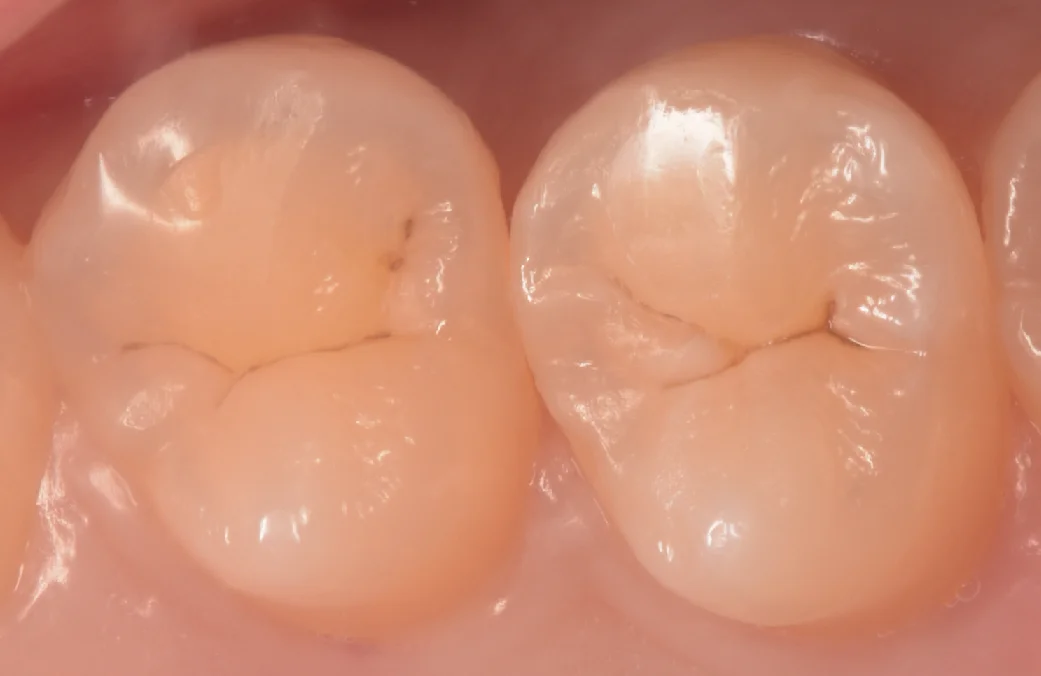

まずは術前からです。

画像中央の歯の間、右側の方に虫歯がありました。

見た目だと全くわからないですよね。

若い方の虫歯の場合、色が白っぽく、全く肉眼ではわからないことがあります。

こういうのをしっかりと見つけるためにはやはりレントゲンとの併用検査が必須だと思います。

術前術後の比較写真がこちらになります。